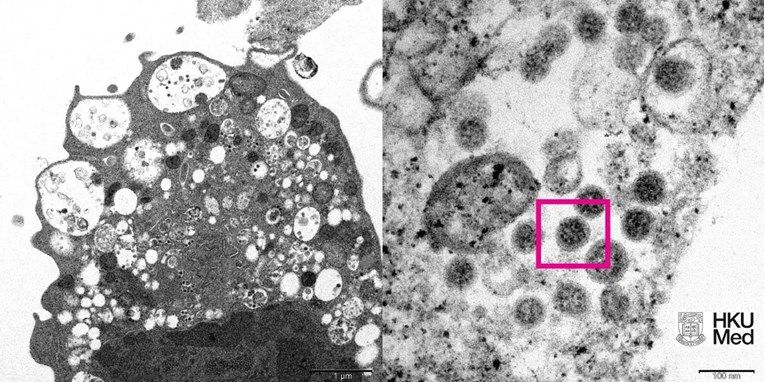

Sveučilište u Hong Kongu danas je objavilo prvu mikroskopsku fotografiju omikrona, nove varijante koronavirusa.

Fotografija omikrona je napravljena elektronskim mikroskopom.

Lijevi dio fotografije prikazuje elektronski mikrograf stanice bubrega majmuna nakon zaraze omikronom. Fotografija prikazuje oštećenje stanice i male crne čestice virusa.

Desni dio fotografije je uvećana verzija lijevog dijela te prikazuje istu zaraženu stanicu. Na tom dijelu fotografije može se vidjeti niz virusnih čestica sa šiljcima karakterističnim za koronaviruse.